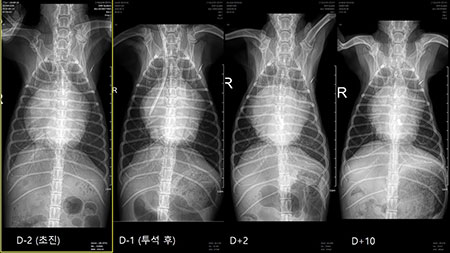

아마 이 아이에게는 모든 순간이 넘어야 하는 높은 산이었을 것이다. 멀리서 내가 할 수 있는 것은 응원 뿐. 그리고 다음날 환자의 방사선 사진이 메시지로 도착했다[그림 2, 3].

투석 만세다. 아이는 잠시 위기에서 탈출했다. 투석을 하면 신장도 위기에서 구해낼 수 있지만 폐수종도 초여과를 통해 해결할 수 있다. 이런 상황을 만들면 단 며칠 이뇨제 요구량도 감소한다.

그래서 이 아이는 어떻게 되었을까? 아이의 수술 전 방사선부터 수술 10일 차의 방사선 사진은 이렇다[그림 5, 6].

이렇게 되었다. stage D 환자에서 이뇨제를 고용량으로 쓰고, 신수치가 많이 오르고, 핍뇨나 무뇨까지 갔던 환자들에게 V-clamp 수술을 해놓으면 어떻게 될까?